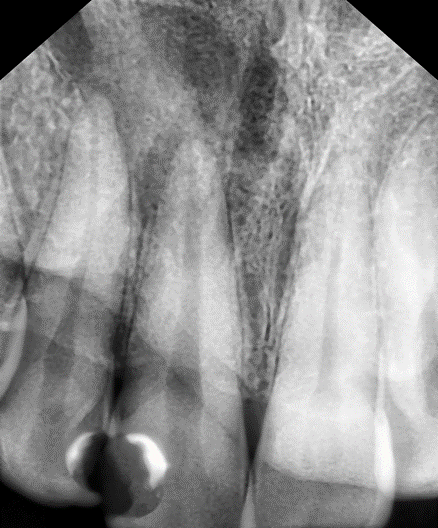

Зуб с кистой на прицельном снимке

На первом визите мы ревизировали зуб с кистой, и всё с ним стало понятно. А для того, чтобы разобраться с кариесом, было сделано достаточно много прицельных снимков.

Зуб с кистой после пломбирования канала

Но вывод о том, насколько успешно прошло лечение и чем нужно изводить её дальше, я смогу сделать не раньше, чем через полгода. И если у меня будет снимок, по которому можно будет судить, уменьшается ли воспалительный процесс. Рассасываться же киста будет до двух лет.